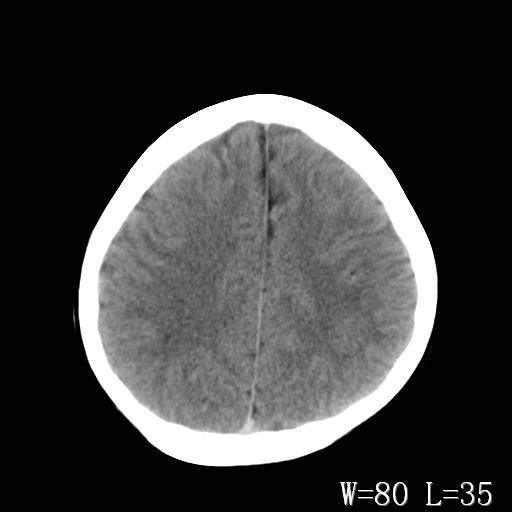

标题: PED3203:脑白质软化?

男,14岁,外伤入院。

双侧枕叶侧脑室旁对称性线状t2高信号 右侧斑点状t2高信号 增强一下可能有点用

支持右侧顶叶后部脑软化灶。

两顶枕区脑白质长t1、长t2信号,基本对称,应考虑脑白质病变,考虑髓鞘发育不良性疾病。且刚外伤,何来之脑软化灶?